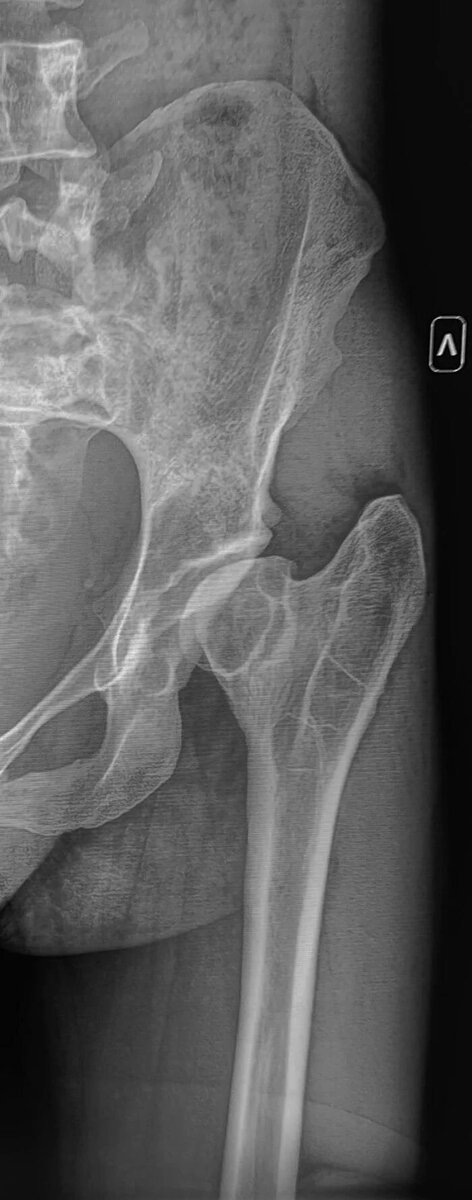

Болезнь Пертеса (полное название: болезнь Легга-Кальве-Пертеса) — это заболевание возникающее в детском возрасте, при котором нарушается кровоснабжение головки бедренной кости, это приводит к ее некрозу и последующей деформации.

Рентгенография левого тазобедренного сустава молодого пациента с жалобы на боли ,ограничение движений в суставе.

Головка левой бедренной кости овоидно деформирована, уменьшена в размере, вертлужная впадина деформирована, уплощена, склерозирована, суставная щель неравномерно сужена. Шейка бедренной кости укорочена, расширена. Заключение: Признаки перенесенной болезни Пертеса левого тазобедренного сустава, вторичный коксартроз слева 2 ст.

Наиболее вероятно такая рентгенологическая картина сложилась вследствие не пролеченной болезни Пертеса в детском возрасте, что привело к деформации головки бедренной кости, вторичным изменениям в суставе.

Категория годности с данным диагнозом по ст.65(Хирургические болезни и поражения костей, крупных суставов, хрящей:)б-В(ограниченно годен к в/сл).